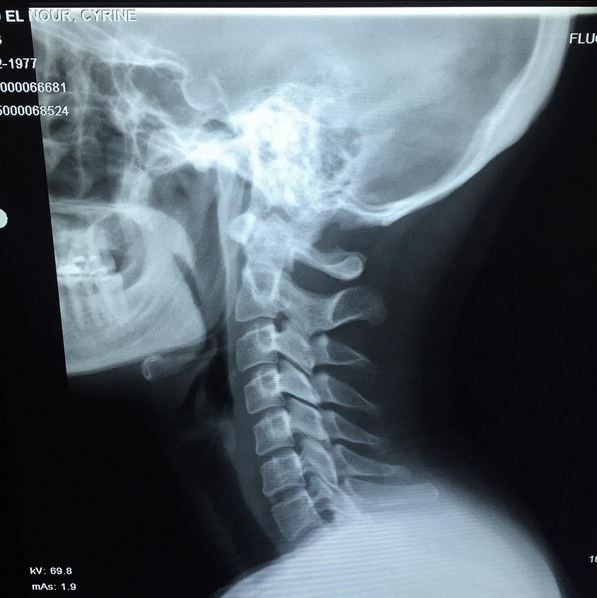

نشرت الفنّانة اللبنانيّة سيرين عبد النور صورة جديدة على "انستغرام" للأشعة السينية لعنقها، معلنة انها مصابة بأوجاع في رقبتها.

وعلّقت عليها قائلة: "صورت رقبتي لأن صرلي فترة حاسة بوجع، والسبب تشنجات بالرقبة، هيك شخّص الدكتور".

وأضافت بطريقة عفوية "بس إنّك تشوف حالك هيكل عظمي وكأنّك ميت شي بخوف".